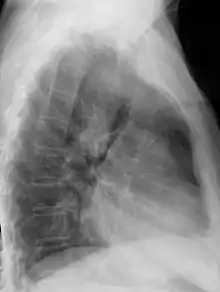

| Anterior-posterior chest radiograph showing a right-sided aortic arch |

After birth, a right-sided aortic arch is visualized on chest radiography, by the aortic knob (the prominent shadow of the aortic arch) that is located right from the sternum instead of left. Complex lesions are often assessed by MRI or CT.